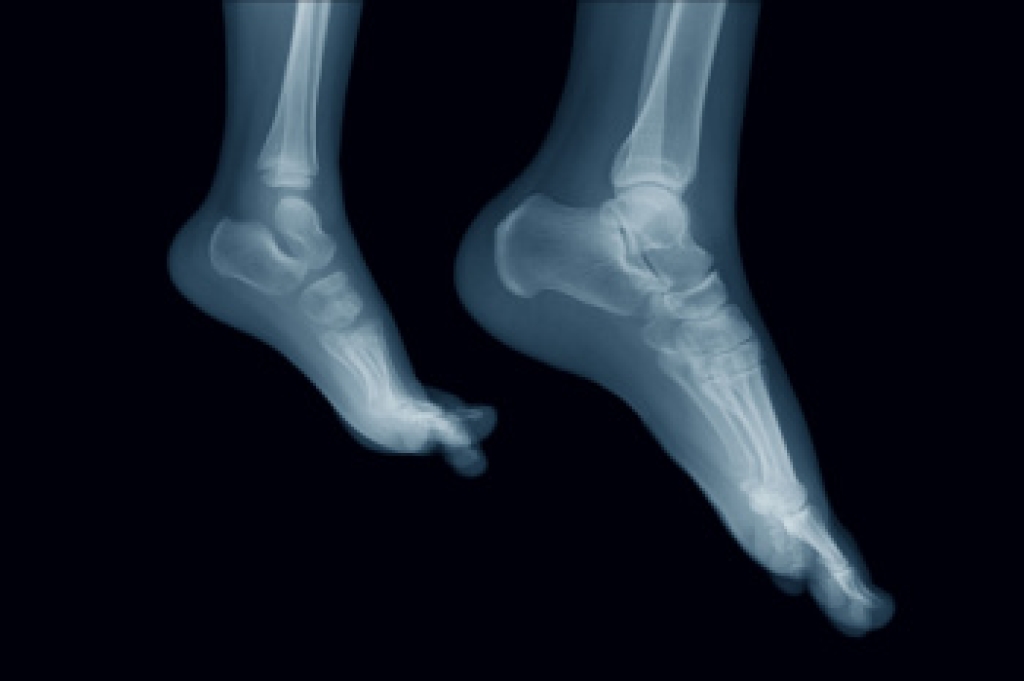

A foot ulcer is an open sore that may appear as a shallow red crater or a deep wound extending to tendon or bone. Ulcers often develop on the bottom of the foot or toes and are most common among people with diabetes, nerve damage, or poor circulation. When sensation is reduced, pressure or friction may go unnoticed, allowing skin breakdown to worsen. Limited blood flow slows healing and increases the risk of infection, cellulitis, or bone involvement. Structural deformities, arthritis, and abnormal walking patterns can also create pressure points that lead to ulcers. A podiatrist evaluates depth, tissue health, circulation, and nerve function, and may order imaging or laboratory testing to detect infection. Treatment includes removing unhealthy tissue, relieving pressure, controlling infection, and addressing biomechanical causes to promote healing and prevent recurrence. If you have developed foot ulcers, it is suggested that you make an appointment with a podiatrist for an exam, diagnosis, and treatment.